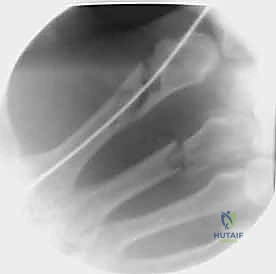

خطوات التثبيت الجراحي - توثيق بصري (Intraoperative Imaging)

يحرص الدكتور هطيف على توثيق خطوات العمل الجراحي لضمان أعلى مستويات الدقة. نستعرض هنا مجموعة من الصور من داخل غرفة العمليات توضح مدى تعقيد ودقة هذه الجراحات:

تتطلب الجراحة انتباهاً خاصاً للأوتار الباسطة والقابضة والأعصاب الدقيقة المحيطة بالعظام. استخدام تقنيات الجراحة الميكروسكوبية (Microsurgery) يضمن عدم الإضرار بهذه الأنسجة الحساسة.

1. التثبيت باستخدام الأسلاك الدقيقة (K-wires)

تُعد هذه الطريقة (Percutaneous Pinning) من التقنيات طفيفة التوغل. يتم إدخال أسلاك معدنية رفيعة جداً عبر الجلد لتثبيت العظم المكسور تحت توجيه الأشعة السينية المستمرة (C-arm) داخل غرفة العمليات.